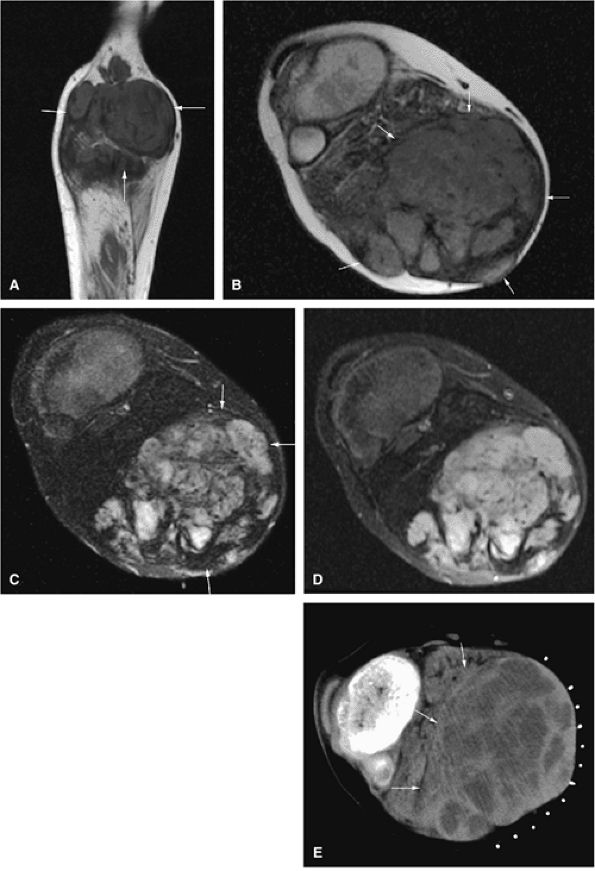

FIGURE 14-73 ● Parosteal osteosarcoma. Anterior coronal (A) and axial (B) T1-weighted images show a large lobulated mass of low signal intensity arising from the metadiaphyseal surface of the tibia (arrows). Tumor is hyperintense on sagittal (C) and axial (D) fat-suppressed T2-weighted fast spin-echo images. Tumor enhancement is noted on axial fat-suppressed T1-weighted image (E) following administration of intravenous gadolinium.

Parosteal osteosarcoma occurs most frequently on the metaphyseal surface of long tubular bones within the parosteal soft tissue and forms a lobulated mass. Histologically it is characterized by a fibrous proliferation surrounding parallel lamellar bony spicules. The fibrous component can appear externally bland, mimicking a fibrous dysplasia. Unlike periosteal osteosarcomas, chondrosarcomatous elements are minimal or absent in parosteal osteosarcomas.99,100

Periosteal osteosarcoma, which accounts for 0.3% of all osteosarcomas, favors the diaphyseal surface of long tubular bones and forms an irregular thickened cortex. Histologically, hyaline chondrosarcomatous elements are a prominent feature.98